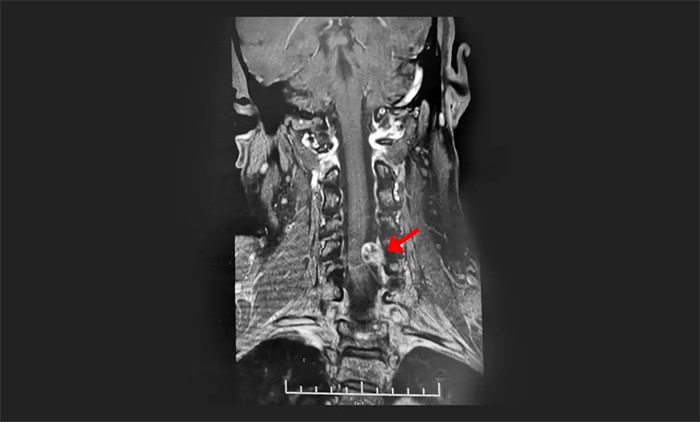

《湖北日報》2023年2月14日報道,60歲的陳阿姨兩年前開始出現(xiàn)雙上肢麻木的癥狀。陳阿姨以為是頸椎病,一出現(xiàn)癥狀她就自行服藥,有時還去按摩,效果不明顯。前段時間,陳阿姨左手臂麻木感越來越強(qiáng)烈,做家務(wù)都有點(diǎn)無力,還出現(xiàn)了胸部麻木和膝蓋疼痛,這才在家人的陪同下來到當(dāng)?shù)厥屑夅t(yī)院求診。經(jīng)頸椎磁共振檢查,顯示頸髓椎管內(nèi)腫瘤病變。

▲ 影像學(xué)檢查是發(fā)現(xiàn)椎管內(nèi)腫瘤較理想的方法

隨著腫瘤壓迫癥狀持續(xù)加重,患者還可出現(xiàn)明顯的運(yùn)動功能障礙。“一些患者以為患上了腦腫瘤或腦血管疾病,殊不知真正的元兇藏在椎管內(nèi)。”于主任表示,通過腦脊液檢查、CT及MRI影像學(xué)檢查、脊髓血管造影等檢查,是可以將椎管內(nèi)腫瘤和頸椎病明確鑒別的。其中,CT或MRI檢查能確定椎管內(nèi)腫瘤的診斷,且能顯示腫瘤與正常組織的界限、腫瘤大小與范圍,是較理想的檢查方法。但這仍然有賴于醫(yī)生扎實的專業(yè)水平和豐富的臨床經(jīng)驗。